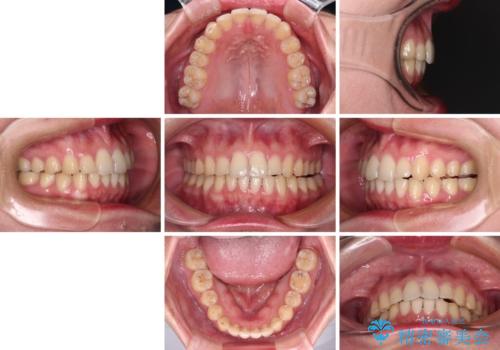

- 食いしばりが気になっていたとのことで来院された患者様です。

当初は睡眠時のマウスピースのみの製作をご希望でしたが、矯正治療の提案をしたところ、インビザラインにて矯正治療を行うこととなりました。

咬合力の緩和と食いしばりがちな咬み合わせが改善され、顎の負担が大幅に軽減されました。